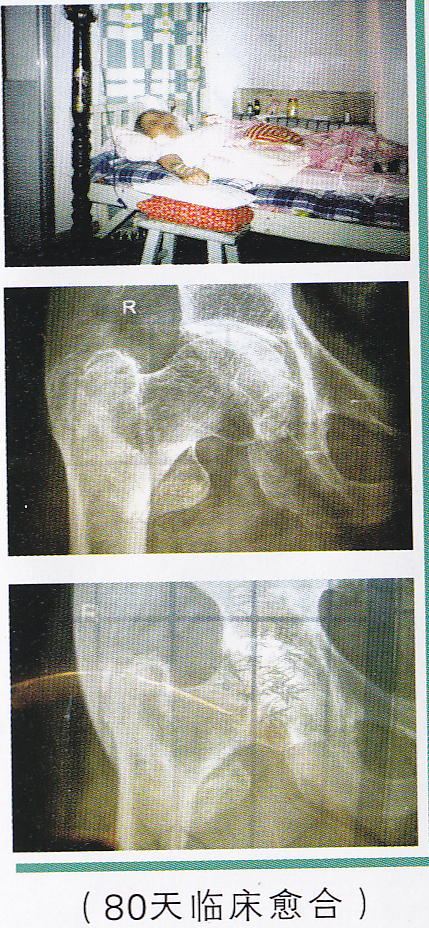

非手术治疗老年人股骨颈骨折的图 非手术治疗老年人股骨颈骨折的图

中医中药有不可替代的优势。通过多年临床验证,笔者在祖传基础上研究出一套治疗老年人股骨颈骨折的中药方剂、方法,克服了骨质疏松、持续牵引导致骨不愈合的难题,治愈率高,无需手术,既经济又减轻了患者的痛苦。